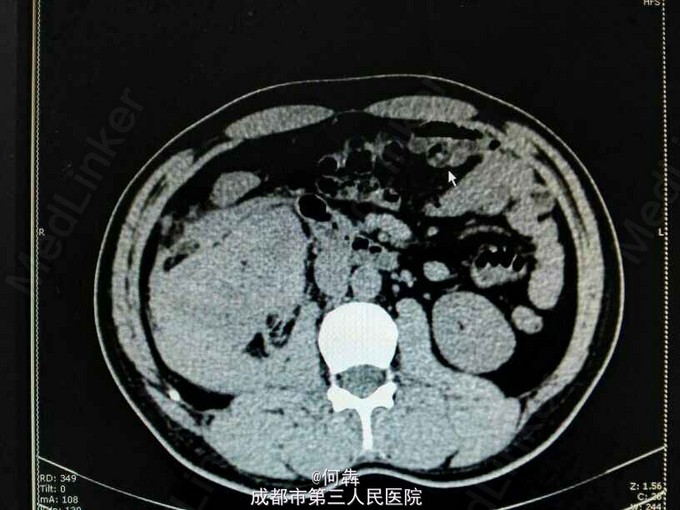

48岁男性,因“突发右腰痛1小时”入院,无血尿、外伤。既往无高血压、糖尿病。

右肾区扣痛阳性,余阴性。

右肾占位伴出血。入院后6天在全麻下行右肾部分切除术。术中冰冻及术后病检见图片

肾上皮样血管平滑肌脂肪瘤(EAML)是肾血管平滑肌脂肪瘤的一种少见亚型。2004版WTO肿瘤分类定义为一种具有恶性潜能的间叶性肿瘤。诊断时则往往与肾细胞癌相混淆。近年较多文献报道,部分EAML易局部复发、侵袭性生长、静脉侵犯、淋巴结或远处转移(以肝和肺转移为主),其预后不佳。